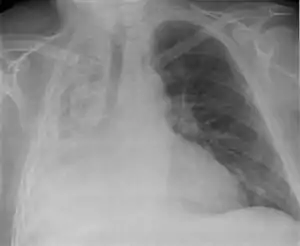

Clinically significant atelectasis is generally visible on chest X-ray; findings can include lung opacification and/or loss of lung volume. Post-surgical atelectasis will be bibasal in pattern. Chest CT or bronchoscopy may be necessary if the cause of atelectasis is not clinically apparent. Direct signs of atelectasis include displacement of interlobar fissures and mobile structures within the thorax, overinflation of the unaffected ipsilateral lobe or contralateral lung, and opacification of the collapsed lobe. In addition to clinically significant findings on chest X-rays, patients may present with indirect signs and symptoms such as elevation of the diaphragm, shifting of the trachea, heart and mediastinum; displacement of the hilus and shifting granulomas.[10]

Compression (relaxation) atelectasis

It is usually associated with accumulation of blood, fluid, or air within the pleural cavity, which mechanically collapses the lung. This is a frequent occurrence with pleural effusion, caused by congestive heart failure (CHF). Leakage of air into the pleural cavity (pneumothorax) also leads to compression atelectasis.[12]